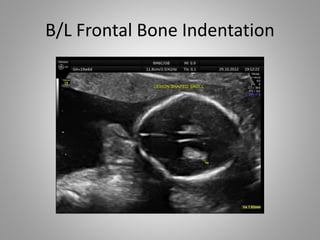

• Head changes in Open Spina Bifida

1. Ventriculomegaly……….........

2. Lemon Sign……………………….

3. Banana Sign………………………

B/L Frontal Bone Indentation

• Head changesin Open Spina Bifida 1. Ventriculomegaly………......... 2. Lemon Sign………………………. 3. Banana Sign………………………

B/L Frontal BoneIndentation